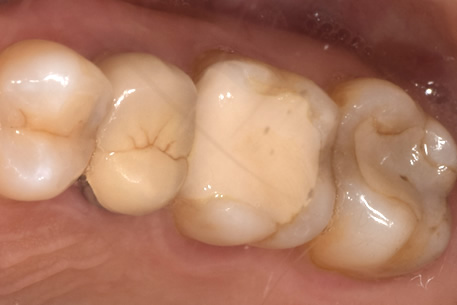

症例① セラミックインレー

治療前

治療後

年齢 60代女性

主訴 歯がしみる

治療方針 つめ物がすでに入っている歯です。そのため、見た目では虫歯があるかどうかわかりませんでしたので、レントゲンを撮影しました。すると、つめ物の中で虫歯になっていることがわかりました。虫歯は、とても大きくなっており神経に近い部分まで進行していました。

治療内容 神経が保存できるかどうか経過をみるために、覆罩といって、神経を守るための処置を行いました。2ヶ月ほど経過を見て、症状が出ないことを確認して、つめ物の型をとり、つめ物をいれていきました。

治療期間 3ヶ月

リスク・副作用 治療後に冷たいものがしみるなどの症状がでることがあります。つめ物を入れた後に痛みなどの症状が出てしまう場合は神経を取り除く治療が必要になります。

費用 ・セラミックインレー:55,000円(税込)

見た目では全くわかりませんが、レントゲンでは黒く抜けて虫歯になっていることがわかります。

虫歯の見分け方

治療中

治療中①

治療中②

治療中①:つめ物をとったところ。茶色い部分は虫歯になっている。

治療中②:染色液を用いて虫歯を選択的に取り除いた。歯はかなりなくなっており、神経近くまで進行していた。

経過観察

虫歯を取り除いた後、神経を守るためのお薬をつめて、2ヶ月ほど経過観察をした。

経過観察中に症状がでなかったため、セラミックのつめ物をいれていった。